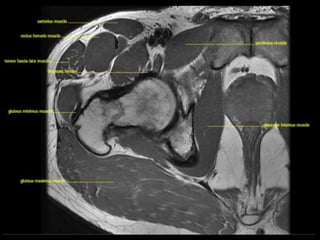

• 120.